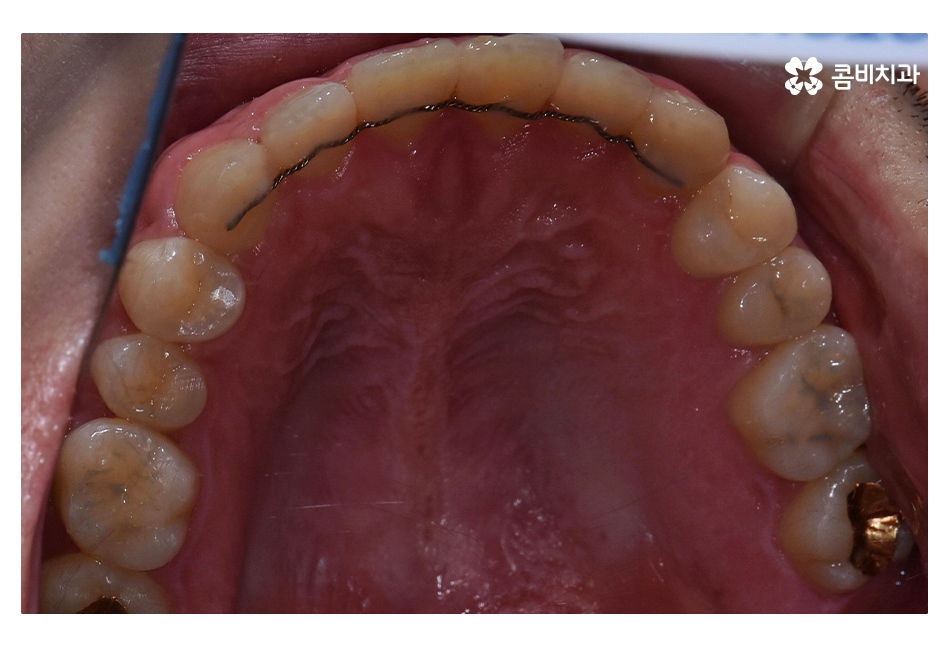

클리피씨교정을 통해서 약 1년 6개월간

치료가 진행이 되었고, 수술과 병행이되며, 치료 마무리 단계에서

임플란트 수술까지 진행이 된 사례라고 볼 수 있는데요.

클리피씨교정은 자가결찰 방식으로 와이어를 고정하고 있으며

일반교정과는 다르게 치아를 이동시킬 때 마찰을

줄일 수 있기 때문에 치아의 이동 속도가 빨라지며

클리피씨교정은 와이어 교체가 간편하며 치아 색과

유사한 세라믹 재질을 사용하기 때문에 심미적으로도 우수한 편이며

일정한 힘을 주어 더욱 빠르게 교정이 가능한 클리피씨교정은

치아교정 환자분들에게 상당히 많이 쓰이고 있는 교정 장치이며